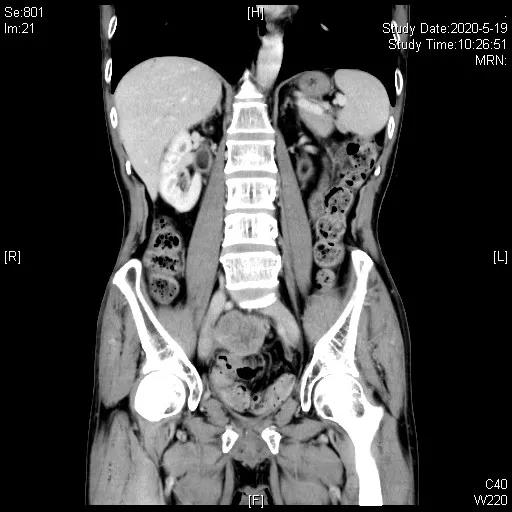

患者二线治疗后进展,TMB>10,拟行免疫治疗,鉴于患者应用抗生素不足1月(末次使用抗生素时间2020.2.20),于2020-03-25、04-21 “吉西他滨1.4d1,1.2gd8+奥沙利铂200mg”化疗2程,并于2020-03-25起,开始予以补充益生菌、调节肠道菌群联合代谢调理治疗等处理。2020-05-19,胸腹部CT示代膀胱壁增厚伴软组织肿块形成,伴双侧输尿管盆腔段受侵、双肾积水,考虑术后复发,肿块较2020-01-16老片增大,近期疗效评估疾病进展(PD),造瘘口有出血。

三线治疗3周期后,影像学评估缩小,PR